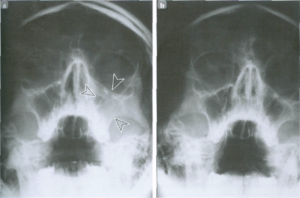

- рентген головы (околоносовых пазух)

Для точной диагностики могут помочь методы визуализации (УЗИ, МРТ, КТ). Они используются, в частности, для определения, в необходимости операции. Более предпочтительной для диагностики синуситов является КТ-визуализация – так как КТ-изображения могут очень точно воспроизводить костные изменения.